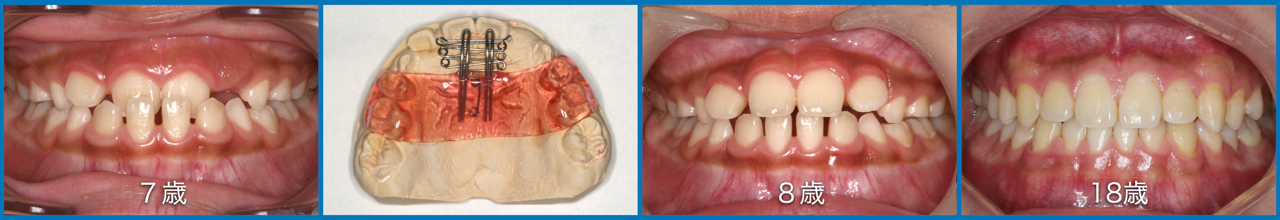

● 咬合育成

子どもたちを虫歯のないきれいな歯並びに誘導していくことが咬合育成で、歯並びが悪くなってから治療する矯正歯科治療とは異なる治療の仕方です。開業時から来院していたこどもたちをどうしたらきれいな歯並びにできるのかを研究してきました。いまではその成果が上がるようになり多くの子どもたちが健康できれいな歯並びをもつ大人になって来院するようになっています。この取り組みは歯科界でも評価され全国の歯科大学や歯科医師会からその分野の講演を依頼されるようになり書籍も出版されて当時はベストセラーになりました。いまでは咬合育成は全国の歯科医院で行われるようになっていますが須貝歯科医院の得意分野になっています。いつもポカンと口を開けて口で呼吸をしていたりするなど、きれいな歯並びになることを妨げる癖もありますがそれらを早く見つけて正しい機能を身に付けさせることも大切です。顎が小さくて歯が並びきらずにガチャガチャの歯並びになってしまうのが日本で一番多い歯列不正です。小さい頃から顎の成長を促す装置をつけて改善することを得意にしています。患者さんによっては矯正専門医に紹介しなければならないケースもあります。その時は地元の信頼できる矯正専門医をご紹介しています。

上の前歯は下の前歯より前にないといけませんが、前歯の生え替わりの時に逆に生えてきましまうことが多くあります。そのままではきれいな歯並びにはなりません。この時が治療のタイミングで、簡単な矯正装置で改善できその後きれいな永久歯列になっていきます。